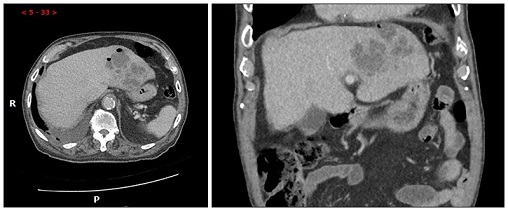

【113-2 醫學(三) 第16題】一位50歲糖尿病人主訴右上腹痛、發燒5天來醫院求診,電腦斷層圖示如附圖,下列敘述何者錯誤?

這是一位有糖尿病史的病人,出現右上腹痛和發燒,電腦斷層(CT)影像顯示肝臟內有大型、邊界不清的低密度病灶,內部不均勻。這些線索強烈指向肝膿瘍(liver abscess)。題目要求找出錯誤的敘述。

選項拆解